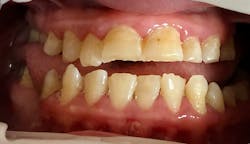

Katie presented with multiple areas of dental decay, heavy plaque buildup, and light to moderate supragingival calculus with little subgingival calculus. There are signs of bruxism with wear and small fractures on her teeth (figures 1 and 2). Katie has a large tongue that often covers her teeth while her mouth is open (figure 3). She has an anterior and posterior crossbite (figure 4) and a retained primary tooth. Katie was cooperative for radiographs, which were taken while working with her verbally and using positive wording and demonstrations. Extra time was taken to allow her to process what was being described and to abate her fears.